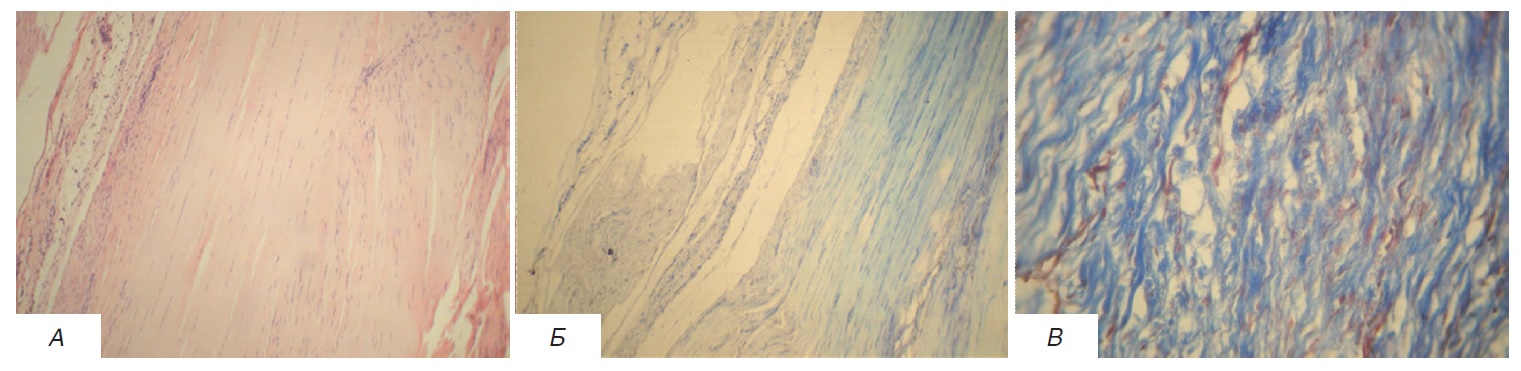

Структурные преобразования ткани сухожилий после моделирования тендинопатии у животных контрольной Г2 заключались в очаговом разволокнении и дезорганизации пучков коллагеновых волокон, мукоидной и липоидной дегенерации, проявляющейся метахромазией при окраске по Массону и толуидиновым синим, а также новообразовании сосудов (рисунок 2). Неоангиогенез, а также лимфоидно-гистиоцитарная инфильтрация с очагами скопления нейтрофильных лейкоцитов характеризовали главным образом участки прилежащего к сухожилию перитенона, окружающие его жировую и мышечную ткани. Гораздо реже очаги воспаления можно было наблюдать непосредственно в самом сухожилии.

Рисунок 2. Пяточное сухожилие животного с экспериментальной тендинопатией. Пучки коллагеновых волокон с участками разволокнения, с очаговой мукоидной и липоидной дегенерацией, очаговой перифокальной лимфо-гистиоцитарной инфильтрацией. А – окраска гематоксилином и эозином, ув. х 100, Б – окраска толуидиновым синим, ув. х 400, В – окраска по Массону, ув. х 100. / Figure 2. Calcaneal tendon of an animal with experimental tendinopathy. Bundles of collagen fibers with areas of disorganization and, with focal mucoid and lipoid degeneration, with focal perifocal lympho-histiocytic infiltration. A – staining with hematoxylin and eosin, x100, Б – staining with toluidine blue, x400, В – Trichrome (Masson) staining, x100.